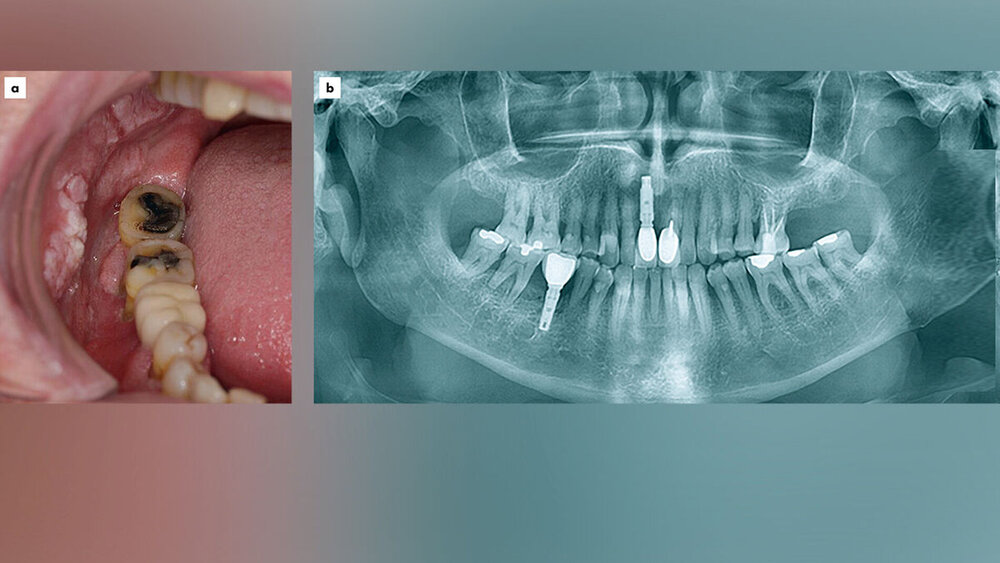

Ein 82-jähriger Patient stellte sich erstmals im Dezember 2017 in der Klinik für Mund-, Kiefer- und Gesichtschirurgie des Universitätsklinikums Freiburg mit einer größenprogredienten Schleimhautveränderung der rechten Wangeninnenseite vor. Die Allgemeinanamnese war bis auf eine arterielle Hypertonie und die Einnahme von Amlodipin und Simvastatin unauffällig. Nikotin- und Alkoholkonsum wurden verneint. Klinisch zeigte sich eine leukoplakische, circa 4 cm x 5 cm große Schleimhautveränderung der Wangeninnenseite rechts sowie des Alveolarfortsatzes von Regio 17 bis 14 und 44 bis 47 reichend (Abbildung 1). Mittels Probebiopsie wurde die Diagnose eines Plattenepithelkarzinoms gestellt.

Nach der Einheilung des Spalthauttransplantats begann die prothetische Phase der Behandlung in der Klinik für Zahnärztliche Prothetik (Abbildung 2). Bei der klinischen Befundung im Rahmen der prothetischen Versorgung zeigte sich Zahn 26 bei Sondierungstiefen von > 7 mm distal, Furkationsbefall und fehlendem knöchernem Attachement an der distobukkalen Wurzel als nicht erhaltungswürdig. Die restlichen Zähne des Ober- und des Unterkiefers (23, 24, 25, 37, 36, 35, 34 sowie 33) waren kariesfrei mit unauffälligen Sondierungstiefen. Die Mundöffnung war nicht eingeschränkt, jedoch zeigte sich in der rechten Wange am Übergang zur Lippe eine circa 8 cm lange Narbe, die jegliches Abhalten auf der rechten Seite durch Narbenzug erschwerte. Auf Wunsch des Patienten wurde zunächst eine festsitzende implantatgetragene Brücke im Unterkiefer Regio 31–45 geplant. Im Oberkiefer wurde aufgrund des geringen Restzahnbestands eine herausnehmbare Steg-/Teleskopprothese mit den Zähnen 23, 24 und 25 als Teleskopen geplant.